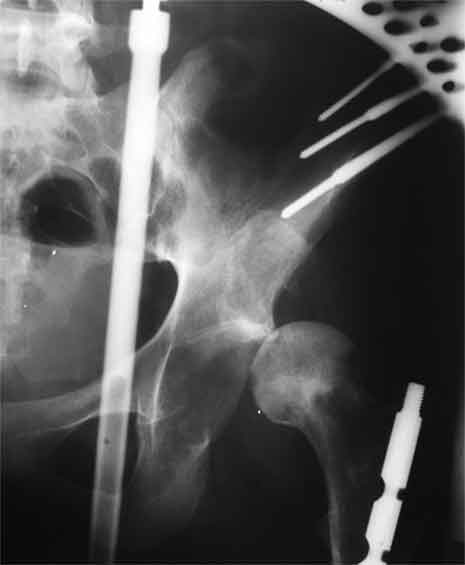

Еще пара фото, ситуация несколько иная, задачи те же, открытое вправление застарелого вывиха в 2002, молодой возраст. Сейчас госпитализирована для эндопротезирования.